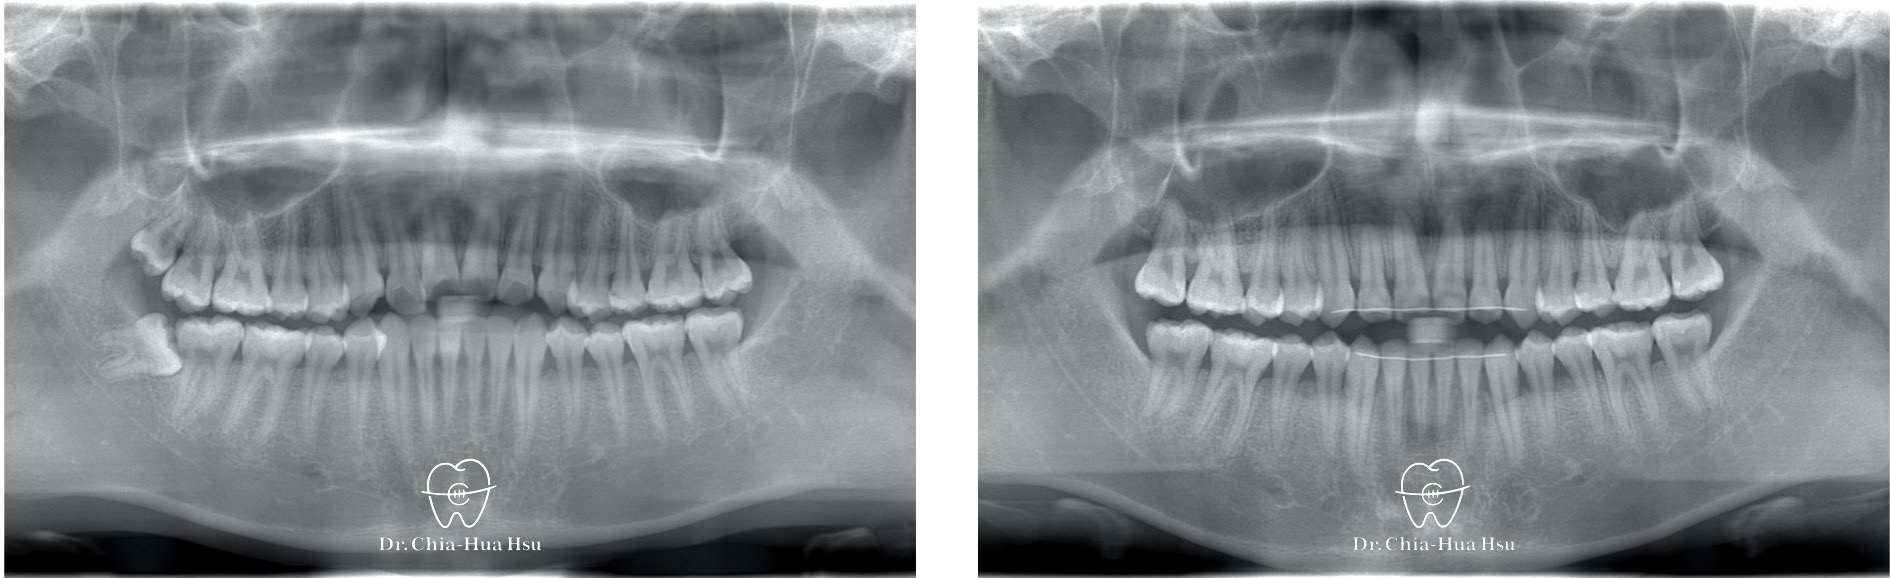

• 病患主訴:前牙錯咬、不整齊,有戽斗臉型,但不想做正顎手術。

• 問題分析:患者是輕微的骨骼三類咬合(Skeletal Class III)、下巴過長(戽斗)、前牙錯咬以及齒列不整齊。

• 治療方式:使用傳統金屬矯正器,並搭配垂直向橡皮筋牽引(Vertical elastics)使牙齒萌出。

• 治療時間:2 年。

• 治療結果:門牙露出增加、齒列排齊 ; 下臉部高度微增使下巴順時針微量旋轉,以修飾戽斗臉型。

治療前

治療後